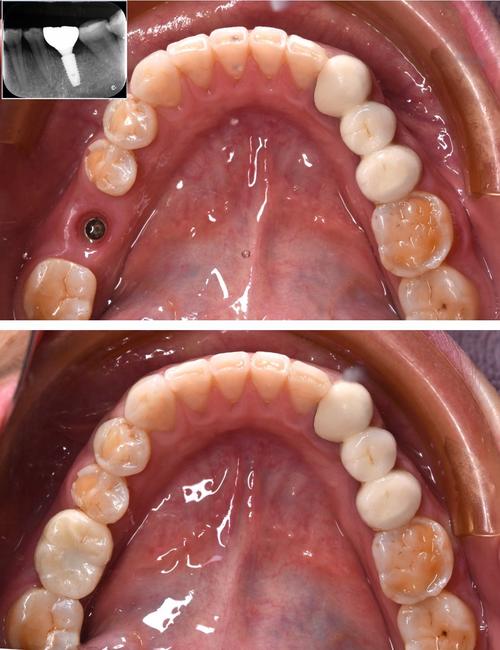

单颗前牙即刻种植

王女士因意外磕断上门牙,影响美观和社交,到牙博士口腔后,医生检查发现牙槽骨条件良好,采用数字化导板即刻种植技术,当天植入瑞士ITI种植体,并临时牙冠修复,3个月后,永久全瓷牙冠佩戴完成,颜色与邻牙一致,形态自然,王女士对效果非常满意。